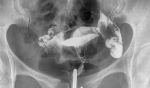

Odebrałam dzisiaj zdjęcia RTG i jaram się patrząc jak się kontrast przelał do otrzewnej. Głupia jestem, cieszę się jakby co najmniej to była ciąża

Kacha opisujesz też zdjęcia RTG czy tylko USG?

Eva82 wrote:Kacha dzięki za wróżbę

Do tego piękna opowieść, prawie jak bajka.